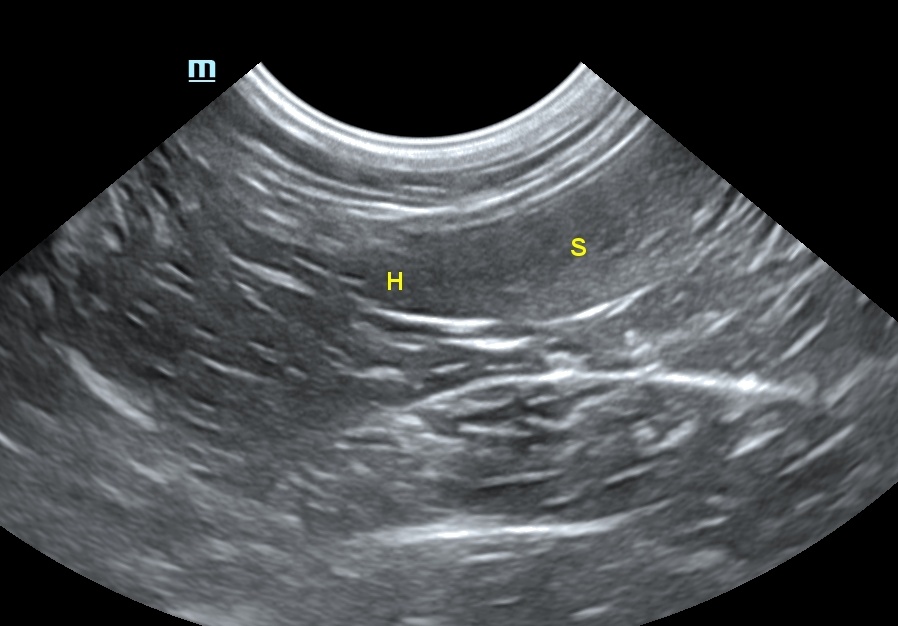

비장의 에코성(echogenicity)은 간과 신장의 에코성과 비교에서 간보다는 높고, 신장보다는 약간 낮습니다(그림 3). 2), 3)

비장의 측정에서 가장 신뢰할 만한 것은 비장의 머리부분을 재는 것이었습니다. 그러나 최근 권장된 최종 프로토콜에는 혈관이 내장 표면에 보일 때 횡단면에서 비장의 근위 1/3 높이를 측정하는 것을 추천합니다.4) 이때 5.1~9.1mm가 되며, 9.1mm 초과 시에는 비장의 비대를 뜻합니다(표 1).